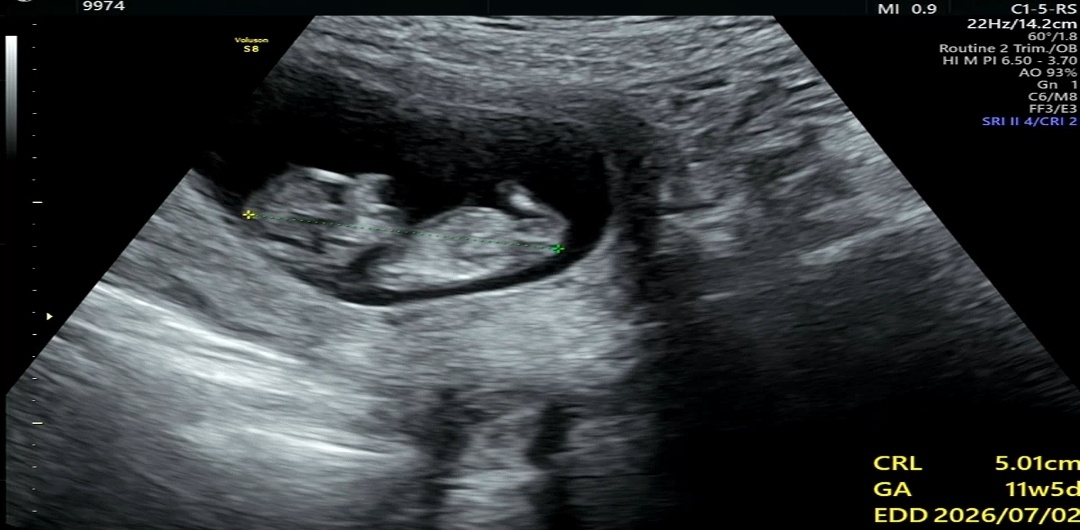

11주차 행운이

병원에서는 주수계산한건 11주3일차인데 오늘 서브병원에서 보니깐 11주5일이네요 지금 행운이가 5.1cm인데 11주3일치고는 큰건가요?.?

어제 주수상으로는 11주 3일이었는데 5.26으로 11주 4일 나왔어요. 주수에 맞게 크는거 같아요.

저 둥이인데 촘파상으로 11주4일이었는데 5cm이랑 4.8cm 이었어요 주수로 계산하면 10주 4일차였어요 ㅎ.ㅎ 비슷한듯..